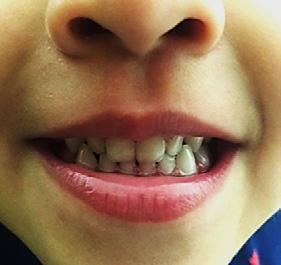

Paciente de 2años y 4 meses, femenino que fue presentada para valoración y consulta, primera dentición y sin caries, presentando hábito pernicioso de protrusión mandibular; normoclusión molar con mordida cruzada anterior (guía canina alterada) (Figura 5). La paciente presentó durante la valoración y consulta una conducta tipo I (- -) según la clasificación de la conducta Frankl y Wright. Mediante una cuidadosa valoración del caso, dada la situación habitual negativa, se diagnosticó como MCA funcional. El plan de tratamiento basado en la posibilidad de realizar un procedimiento práctico y adecuado fue el de realizar solo un ligero y cuidadoso desgaste de los puntos de contacto en la cúspide canina y distal de

Figura 5. A) Posición de los caninos inferiores alterando la guía. B) Guía canina liberada tras el ajuste oclusal en ambas cúspides caninas inferiores. C) Protrución del labio. D) Retrución de labio una semana después.